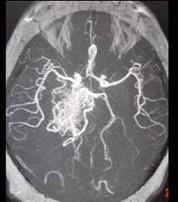

女性,40岁,头晕、头痛两年余,MR检查如图所示,请选择的最可能诊断 ( )A、毛细血管扩张症B、动脉瘤C、动静脉畸形D、毛细血管...

问题 女性,40岁,头晕、头痛两年余,MR检查如图所示,请选择的最可能诊断 ( )

选项 A、毛细血管扩张症 B、动脉瘤 C、动静脉畸形 D、毛细血管瘤 E、海绵状血管瘤

答案 C